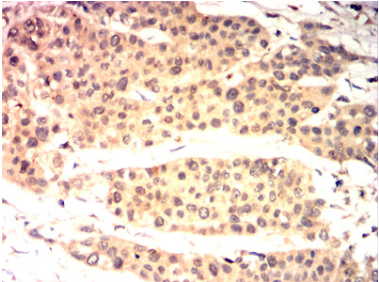

IHC    1/200 - 1/1000